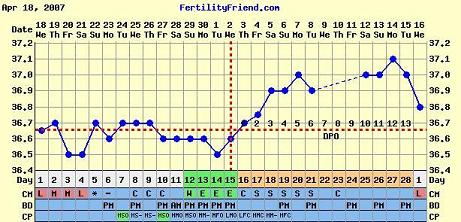

Rólam: Piri sehol. Holnap megyek vérvételre. ELEGEM VVVAAANNNNN!!!!!!!!!!!!!